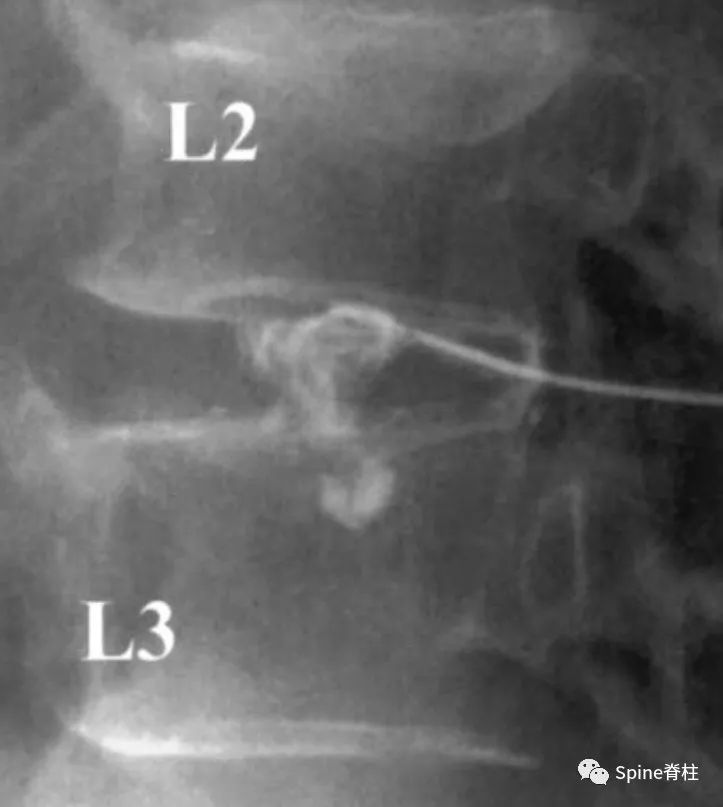

“黑椎间盘”是不是疼痛的?通常需要椎间盘造影或阻滞来明确或排除。虽有争议,目前腰椎间盘造影术仍是诊断椎间盘源性腰痛的“金标准”。椎间盘造影诱发平时疼痛是明确疼痛椎间盘的有效方法,或者椎间盘内注射*醉药麻**(比如布比卡因)后平时的腰痛症状明显消失。疼痛的椎间盘在造影剂注射过程中,造影剂要么通过放射状纤维环撕裂流向椎间盘外方,要么通过放射状终板撕裂流向椎体,两者都诱发患者平时的腰痛反应。这也是鉴别终板源性腰痛和由纤维环撕裂引起的椎间盘源性腰痛的主要手段。

图:椎间盘造影时,造影剂流至破损的终板